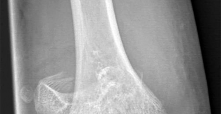

A 9-year-old male presents with acute shoulder pain after throwing a baseball. Radiographs reveal a pathologic fracture through a centrally located, lytic, expansile bone lesion in the proximal humeral metaphysis. A "fallen leaf" sign is noted. What is the most appropriate initial management?